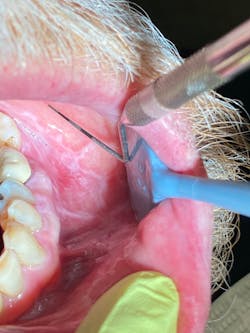

Clinically, the lesions were generalized, more prominent in the posterior buccal vestibular areas. White patches and collective striations were seen, measuring from 4 mm to 12 mm in size. They were painful to the touch and did not rub off with gauze. The patient said he noticed the start of the lesions on the tip of his tongue and on his lower lip, which appeared to be cracked and dry. See accompanying images.